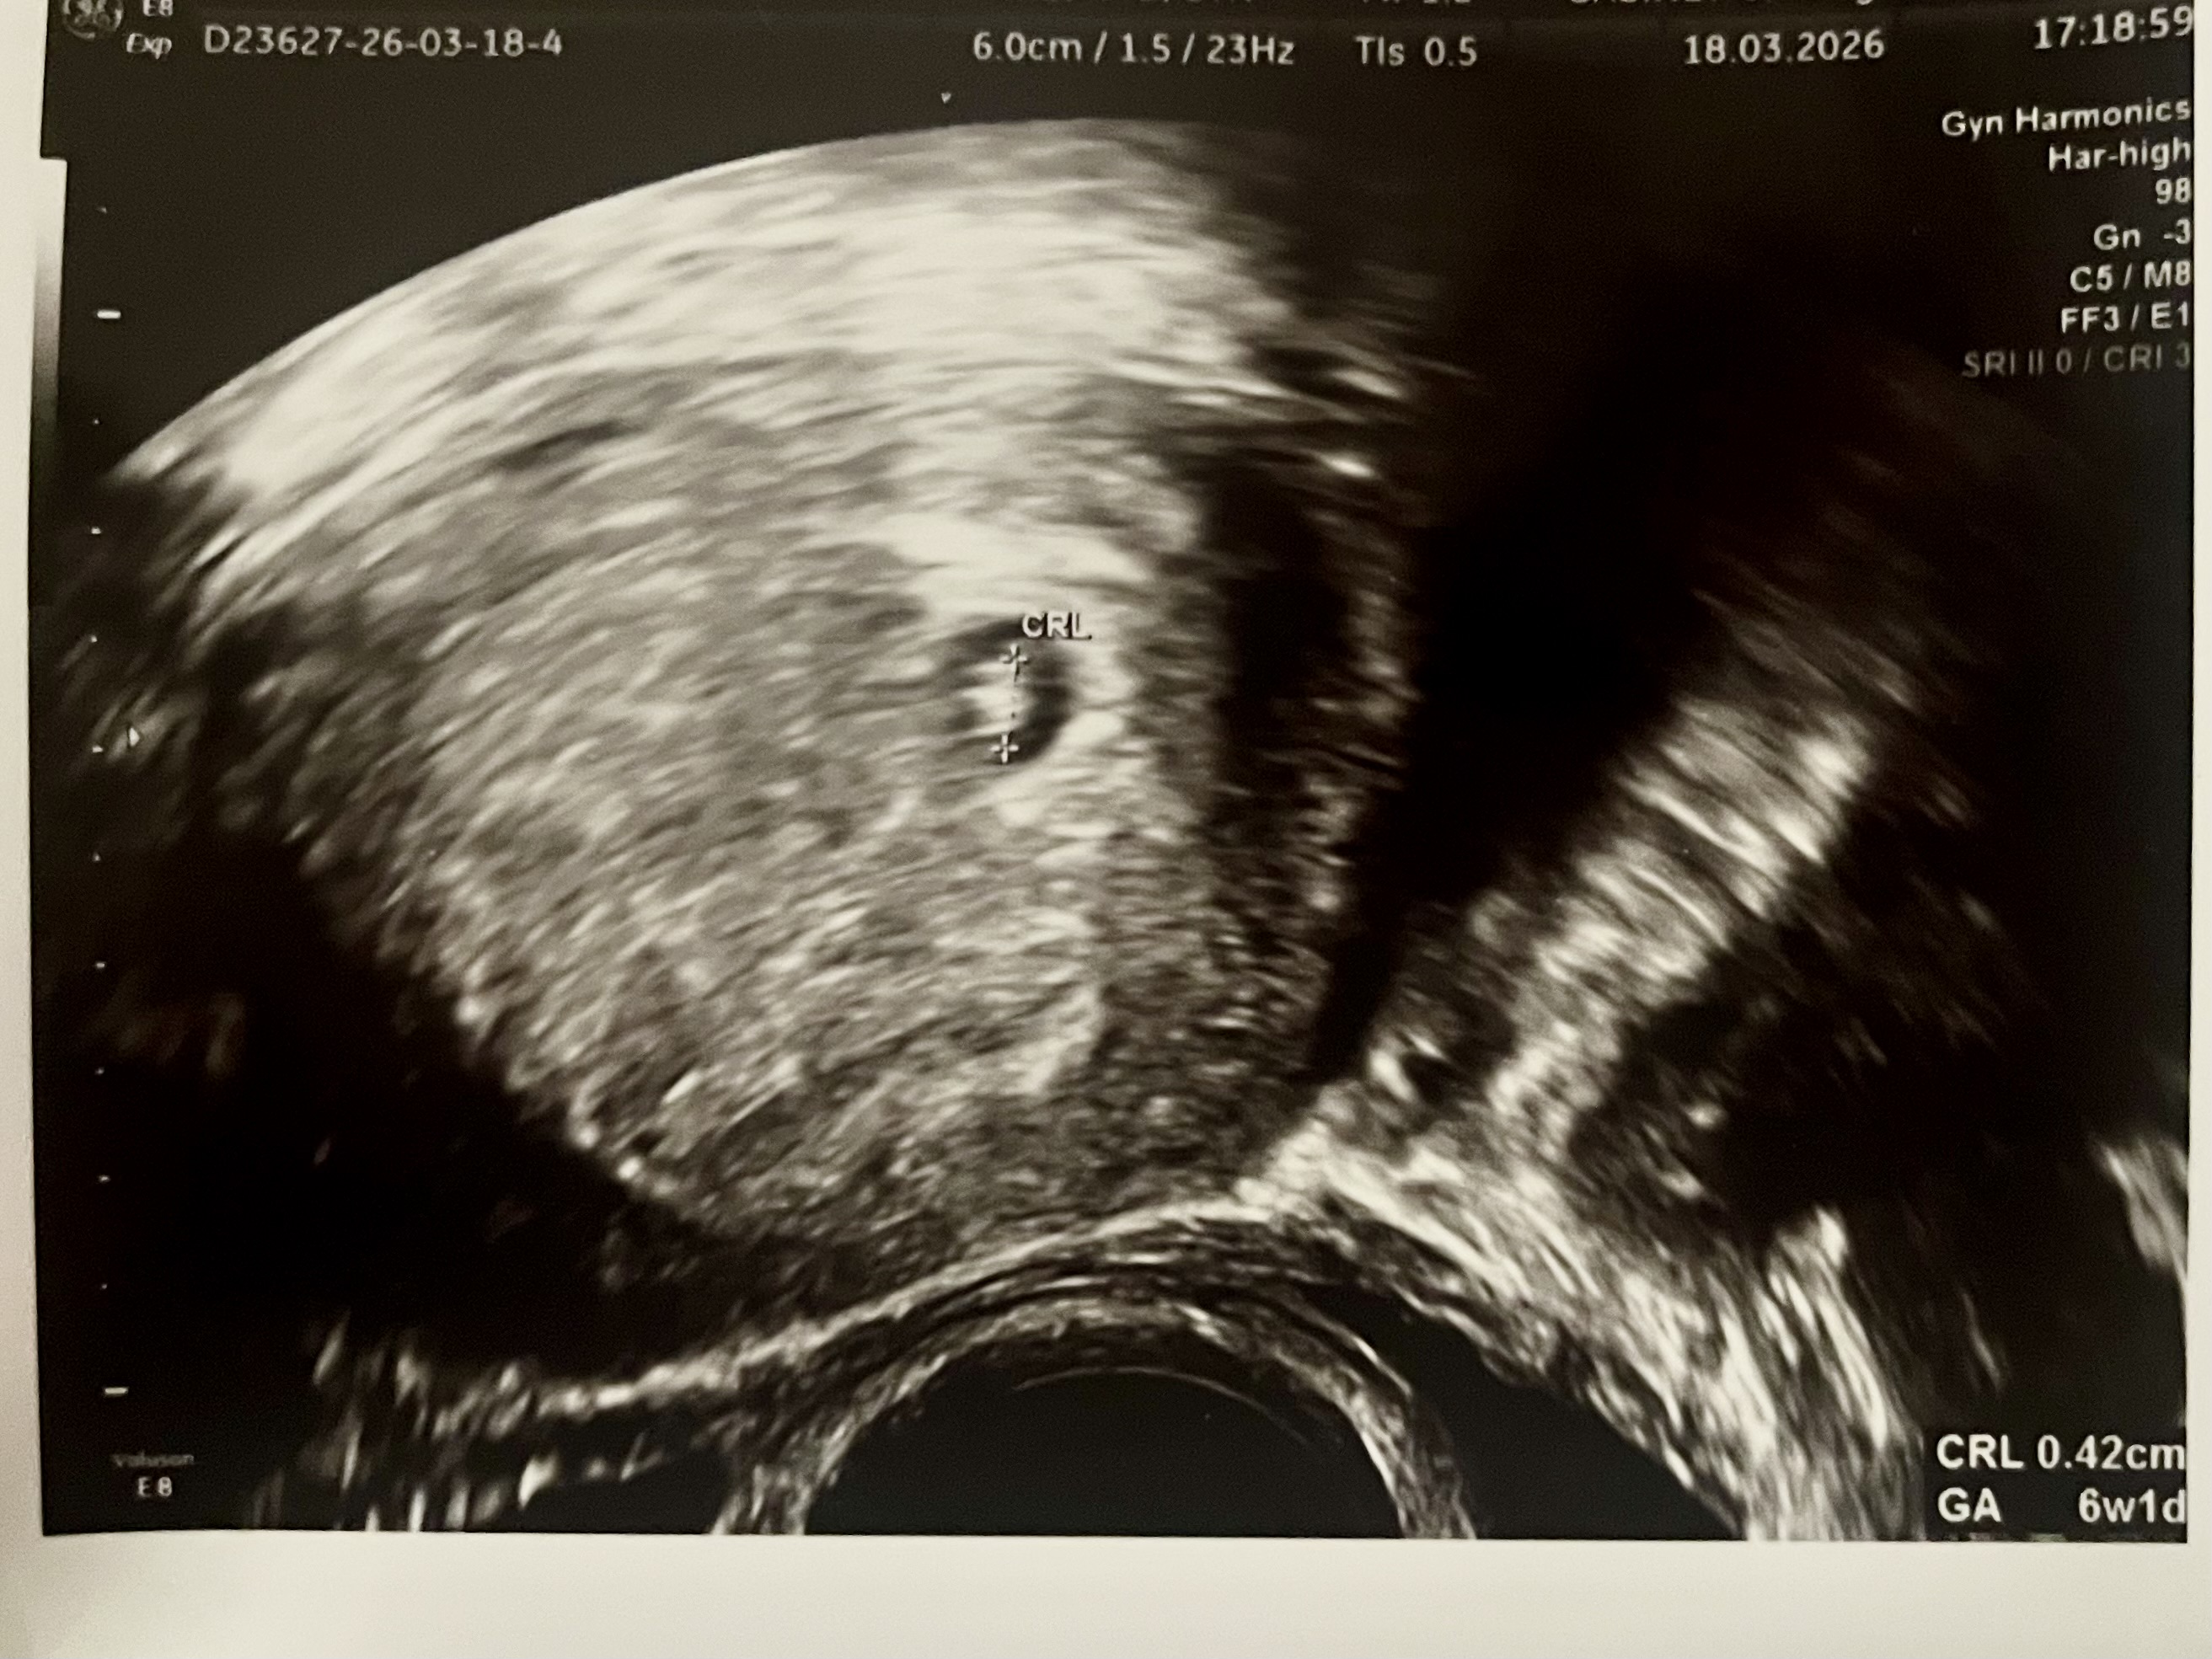

No i co jeszcze po wizycie - no mamy to

Jegomość bądź Jegomościna ma 4 mm

Z widocznym tętnem

Zobacz załącznik 1738107